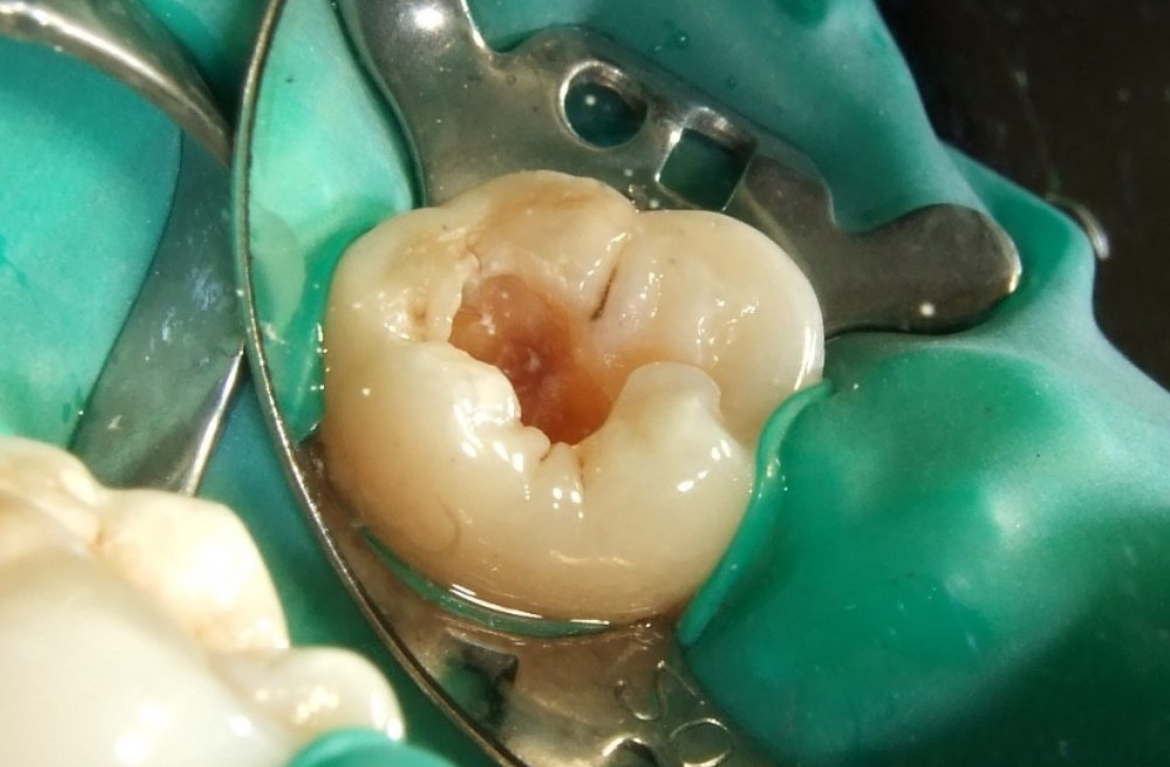

Root Canal Treatment + Dental Filling Image

Root canal treatment combined with dental filling is a highly effective solution for saving damaged or infected teeth. The procedure involves removing the infected pulp, cleaning and disinfecting the root canals, and sealing the space with a durable filling material.

This treatment not only eliminates pain and infection but also restores the tooth’s function and appearance. It’s typically completed in a single session, ensuring fast relief and protection against further complications. With advanced tools and experienced professionals, we guarantee a comfortable and successful root canal experience.